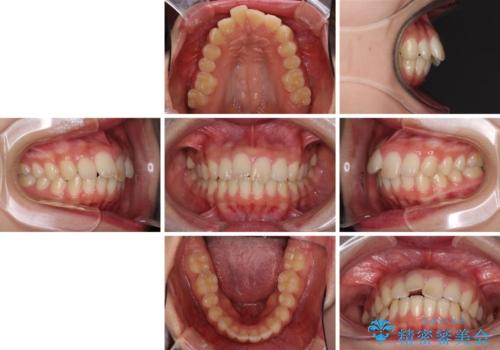

就職前にきれいな歯並びにしたい 大学生のインビザライン矯正

- 就職するまでに歯並びをきれいにしたいとのことで来院された患者様です。

前歯の叢生を気にしていましたが、極力突出感を改善できるようにすることとし、インビザラインにて矯正治療を行うこととしました。

改善の期待できない口元の突出感改善を希望されたため、いたずらに治療期間が延びましたが、きっちりと仕上がりました。

- 2年4ヶ月